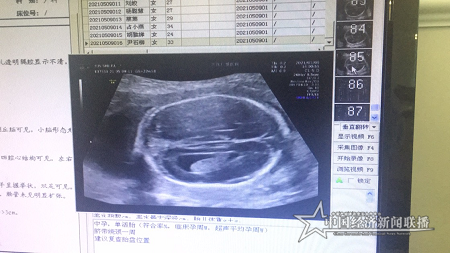

胎儿十二指肠闭锁声像图

据了解,当天上午,检查完赵女士(化名)后,超声科主任王娟告诉她,四维彩超片显示,腹中胎儿十二指肠呈扩张状态,胃泡也有明显扩张,另外扩张的胃泡以及十二指肠之间,有一长条形囊状结构相连,患儿还出现羊水过多等症状。原本满心欢喜的赵女士,顿时陷入痛苦中。